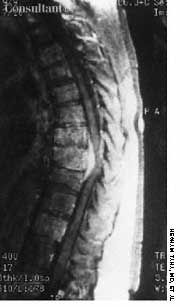

An obese woman presented with worsening midline back pain. This MRI scan shows a spinal epidural abscess (white arrow). Diabetes mellitus was her only risk factor. Her presentation, including an initial miss by her primary care physician, is fairly classic.

Image courtesy of Brady Pregerson, MD.